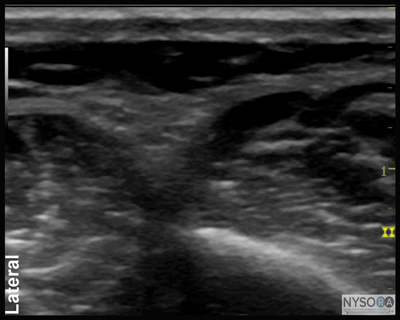

Figure 7:Transducer position and needle insertion to block the superficial peroneal nerve. ![]() Figure 8: Cross-sectional anatomy of the superficial peroneal nerve (SPN). EDL, extensor digitorum longus muscle; PBM, peroneus brevis muscle. Superficial Peroneal Nerve The superficial peroneal nerve innervates the dorsum of the foot. It emerges to lie superficial to the fascia 10 to 20 cm above the ankle joint on the anterolateral surface of the leg. A transducer placed transversely on the leg, approximately 5 cm proximal and anterior to the lateral malleolus, will identify the hyperechoic nerve lying in the subcutaneous tissue immediately superficial to the fascia (Figures 7, 8, and 9A and B). If the nerve is not readily apparent, the transducer can be traced proximally on the leg until, at the lateral aspect, the extensor digitorum longus and peroneus longus muscles can be seen with a prominent groove between them leading to the fibula (Figure 10A and B). The superficial peroneal nerve is located in this intermuscular septum, just deep to the fascia. Once it is identified at this more proximal location, it can be traced distally to the ankle. Because the superficial nerves are rather small, their identification with ultrasound is not always possible in a busy clinical environment. Sural Nerve The sural nerve innervates the lateral margin of the foot and ankle. Proximal to the lateral malleolus, the sural nerve can be visualized as a small hyperechoic structure that is intimately associated with the small saphenous vein (Figures 11, 12, and 13A, B). A calf tourniquet can be used to increase the size of the vein, aiding in identification of the nerve. Saphenous Nerve The saphenous nerve innervates the medial malleolus and a variable portion of the medial aspect of the leg below the knee. The nerve travels down the medial leg alongside the saphenous vein. Because it is a small nerve, it is best visualized 10-15 cm proximal to the medial malleolus, using the saphenous vein as a landmark (Figures 14, 15, and 16A, B). A proximal calf tourniquet can be used to assist in increasing the size of the vein. The nerve appears as a small hyperechoic structure.

Figure 10: (A) Ultrasound anatomy of the superficial peroneal nerve. (B) Ultrasound anatomy of the nerve with structures labeled. EDL, extensor digitorum longus muscle; PBM, peroneus brevis muscle; SPN, superficial peroneal nerve.